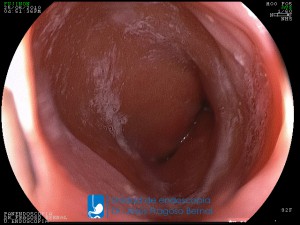

La Unidad de Endoscopía fue creada en 2002 por el Dr. Jesús Fragoso Bernal, es pionera en el estado por la utilización de la tecnología más avanzada, que nos permite ofrecer servicios integrales de diagnóstico y tratamiento para las enfermedades del aparato digestivo.

El profesionalismo de nuestro personal, altamente especializado, se distingue por la calidad y calidez de nuestros servicios con el objetivo de brindar una atención de excelencia en el ambiente más confortable para comodidad y seguridad de nuestros pacientes.